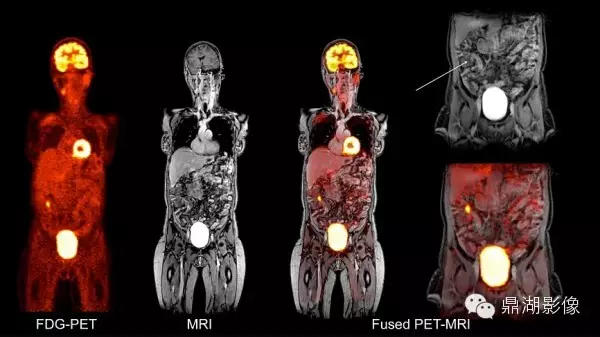

4.PET—MRI设备:PET-MRI是将PET(正电子发射计算机断层显像)的分子成像功能与 MRI (核磁共振成像)卓越的软组织对比功能结合起来的一种新技术。

一体化PET—MRI是将PET和MRI有机组合在同一个机架内,在MRI变化不大的前提下,重新设计PET探测器以适应MRI的高磁场、高射频场和高梯度切换,将PET探测器集成在MRI的射频体线圈和梯度线圈之间,一次扫描即可同时完成PET和MRI检查,可获得人体有关解剖、PET/MRI检查与其他手段相比,它的灵敏度高、准确性好,对许多疾病(尤其是肿瘤和心脑疾病)具有早期发现、早期诊断的价值。

这是一例PET-MRI诊断的盲肠炎患者,在融合后发现盲肠区域有小片状的炎症性改变,但在独立的MRI图像和FDG-PET图像上很难显示。

Images provided by Drs. Alex Guimaraes, Ciprian Catana, Bruce Rosen, and David Berger (Massachusetts General Hospital, Boston, MA).